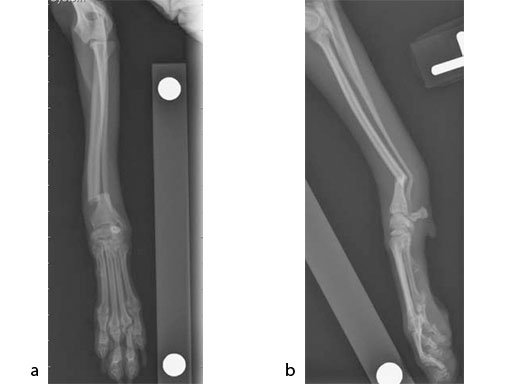

The patient was an approximately 2-year-old 1.5 kg miniature poodle with a radius and ulna fracture of the left thoracic limb. Although there are (1.5 mm screw) cuttable plates available for these small breeds, they require disruption of the periosteum and sometimes the distal fragment has room for only one screw if a straight plate is used. The tiny T plates, using cortex screws, are often too short; ideally at least 3550% of the limb length has to be spanned. In traditional plates, every hole must be filled and contributes to stress protection of the bone. These plate options also do not permit the use of locking screws. Therefore, the condylar LCP 1.5 was a perfect plate for these fractures (Fig 7).

An open but do not touch approach was performed with 3 proximal screws and 2 distal locking screws inserted in the LCP (Fig 8).

After 3 months, the previous fracture of the radius was no longer visible and there was smooth callus in the region of the previous fracture (Fig 9). There was bone loss at the distal ulna, most likely due to stress shielding. Plate removal can be considered at 6 months if bone resorption is a concern.